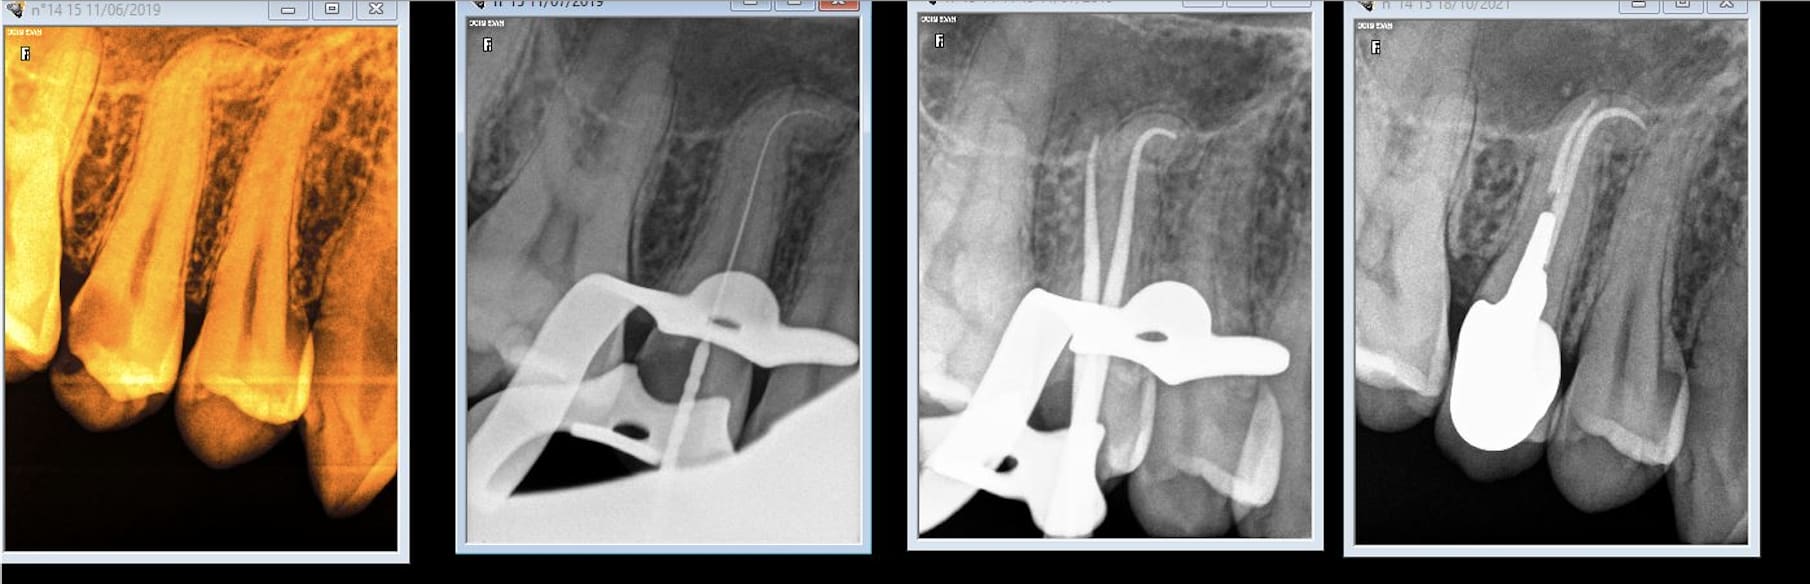

Ce matin reprise de traitement de 16 pour un ami qui habite la Suisse.

Un lentulo cassé dans la racine palatine, obturation sur 4 mm sur la mp et rien sur la dp.

C'était la rte en France ou extraction implant en suisse.

Et surtout formes toi auprès de ceux qui savent faire et qui nen font beaucoup avec des résultats reproductibles. En une semaine je dois faire les endos que fait un prof en 6 mois. -)

Pugilat mis à part, la difficulté de l'endo est surévaluée. A vu de nez, 90% se gèrent sans soucis si on bosse consciencieusement et bien équipé. Quand je vois une endo à mi racine et un canal d'un mm de diamètre qui continue jusqu'à l'apex sur une pano, pas besoin d'avoir vu 600 traitements pour faire mieux.

Reste 5% d'endos merdiques prévisibles à adresser, et 5% imprévisibles qu'il faudra identifier le plus tôt possible avant d'avoir fait une perfo ou pété une lime.

Tu le dis toi même, un bon praticien a des résultats reproductibles, et c'est pour moi plus une question de technique que d'expérience, même si cette dernière aide évidemment à acquérir la première.

Les endos pourris que je vois passer, c'est avant tout le résultat de praticiens qui s'en foutent.

Bon, chapeau pour la 2ème qui a une séparation des canaux assez basse qui a du être assez pénible à préparer et la négociation de la courbure de la 4ème. Les autres ont 2 canaux mais l'accès semblait relativement aisé et leur naissance assez haute pour qu'on ne puisse pas vraiment les rater.

Et très sérieusement et je pose la question car je me la pose vraiment, pour chacune de ces dents, est-ce que tu considères qu'elles ont été difficiles à traiter?

J'entends par là avec un risque d'échec (casse, oubli de canal, obturation incomplète, ...) élevé qu'un praticien lambda consciencieux qui aurait pris le temps nécessaire n'aurait pas sur gérer, et que toi tu as su gérer uniquement grâce à ton expérience (et tes formations peut être?) ?

Aucune, mais ça serait plus simple si à la base on t'apprenais à les faire correctement. -)